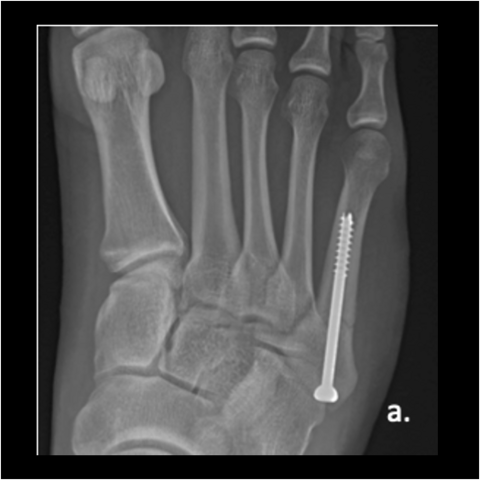

Figure 3a

Figure 3a. A 28-year-old Army officer injured during combatives was able to walk 2 days post-surgery. He started wearing his Army boots 2 weeks after surgery and completed Sapper School 10 weeks after surgery. He then went to Special Forces training within 6 months postop. The patient never had any pain after surgery. Here is the foot when the patient got injured.